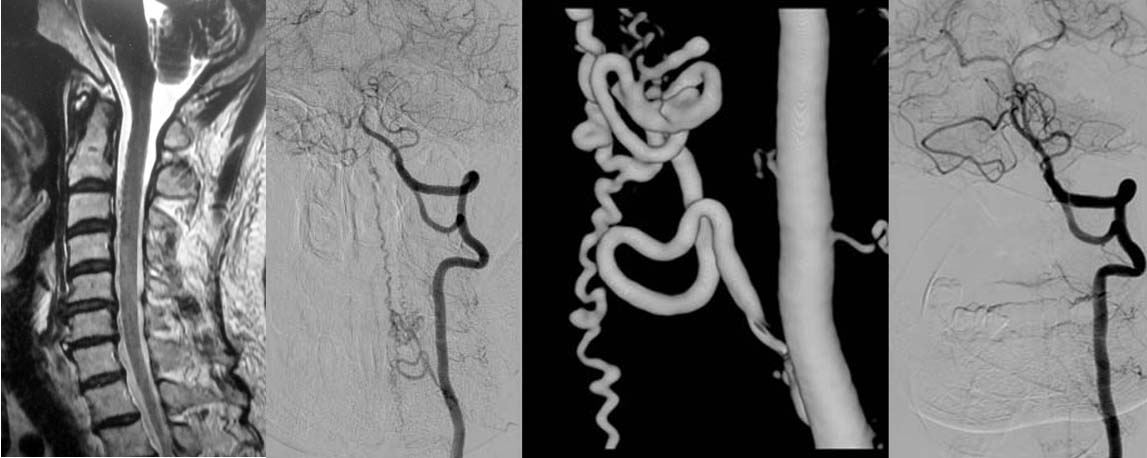

図1.頚椎MRIでは脊髄の周辺にプツプツとした小さな陰影がみられますが、詳細はわかりません。造影剤を用いたカテーテル検査(左椎骨動脈撮影)では異常血管が描出され、脊髄硬膜動静脈瘻であると診断できます。下記手術を行い、異常血管は消失しました。

神経所見を診察し、MRI等を施行し脊髄梗塞や出血の診断をします。しかし、脊髄の血管は細かいためMRIだけでは診断は難しく、造影剤を用いたカテーテル検査が必要です。